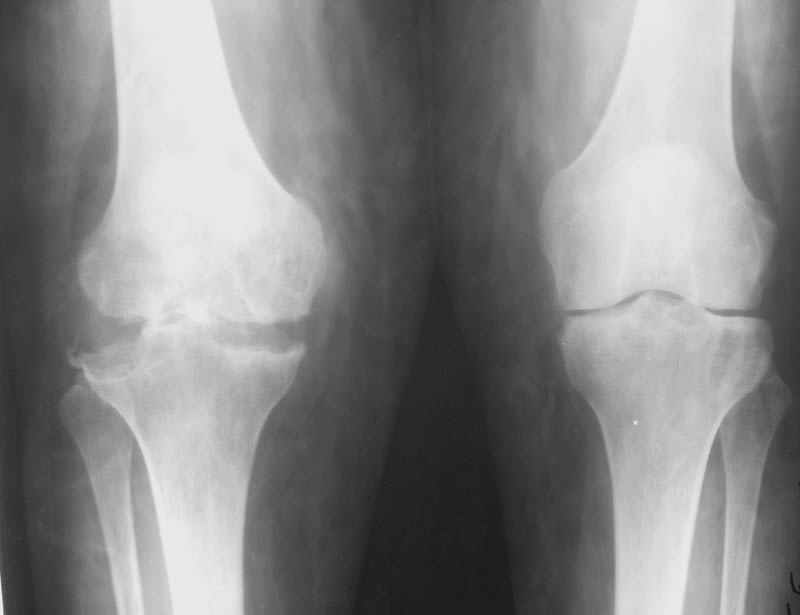

Уважаемые коллеги! Женщина, 28 лет. Страдает ревматоидным полиартритом, гормонозависима. 6 месяцев назад перенесла тотальное эндопротезирование левого тазобедренного сустава по поводу протрузионного коксита.

Использована цементная версия с пластикой дна впадины измельченной аутокостью и гранулами гидроксиапатита. Субъективное улучшение после операции. Улучшилось и стабилизировалось общее состояние. В настоящее время затруднено передвижение из-за поражения правого коленного сустава. Болезненный и <болтающийся> сустав. Предполагается замена сустава протезом без сохранения задней крестообразной связки. Возможные варианты? Заранее благодарю! С уважением,А.В.ВладзимирскийДонецкий НИИ травматологии и ортопедииДонецк, Украина

В случаях ревматоидного артрита с деструктивными изменениями сустава мы стараемся применять конструкции типа RT-Solution (Plus) или AGC (Biomet) из-за высокой вероятности нестабильности также и коллатеральных связок. Эти эндопротезы не требуют сохранения связок вообще. Выбор обусловлен также исходной вальгусной (варусной) деформации.